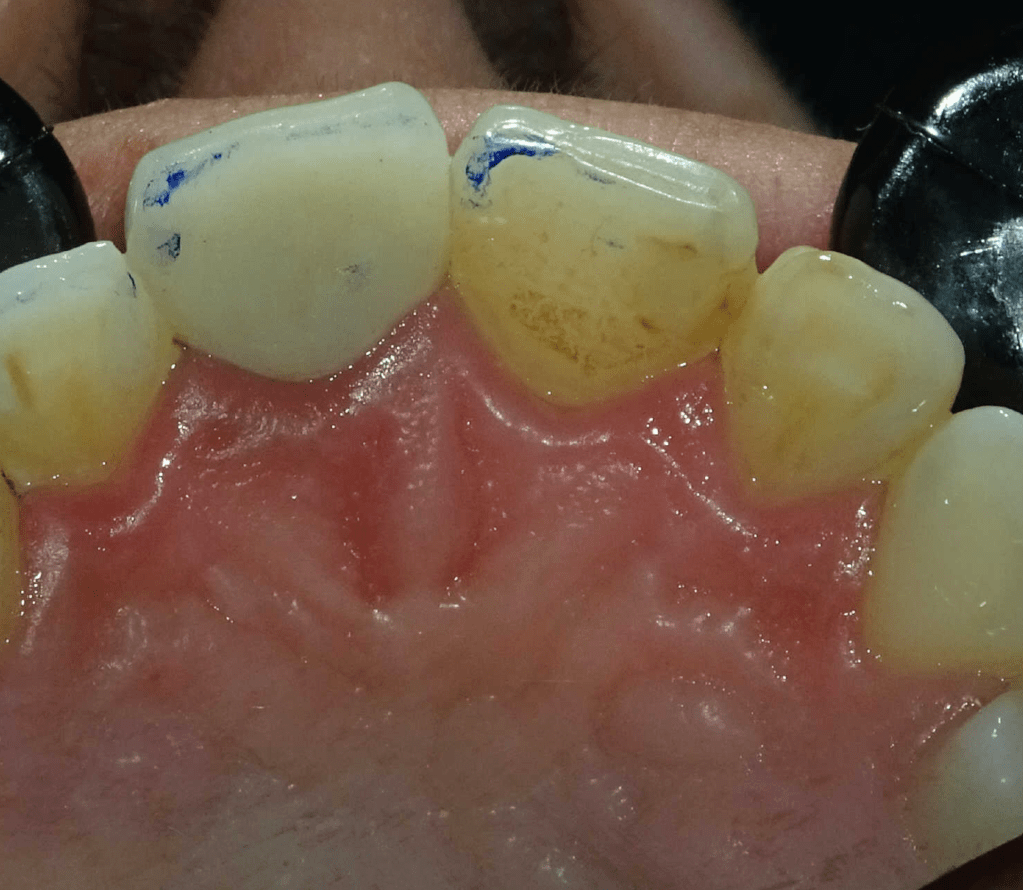

Reconstrucción preendodóntica

Reco pared vesticular

Reco pre-endo gingivectomái, pared yuxtaosea

Reco preendo + gingivectomía